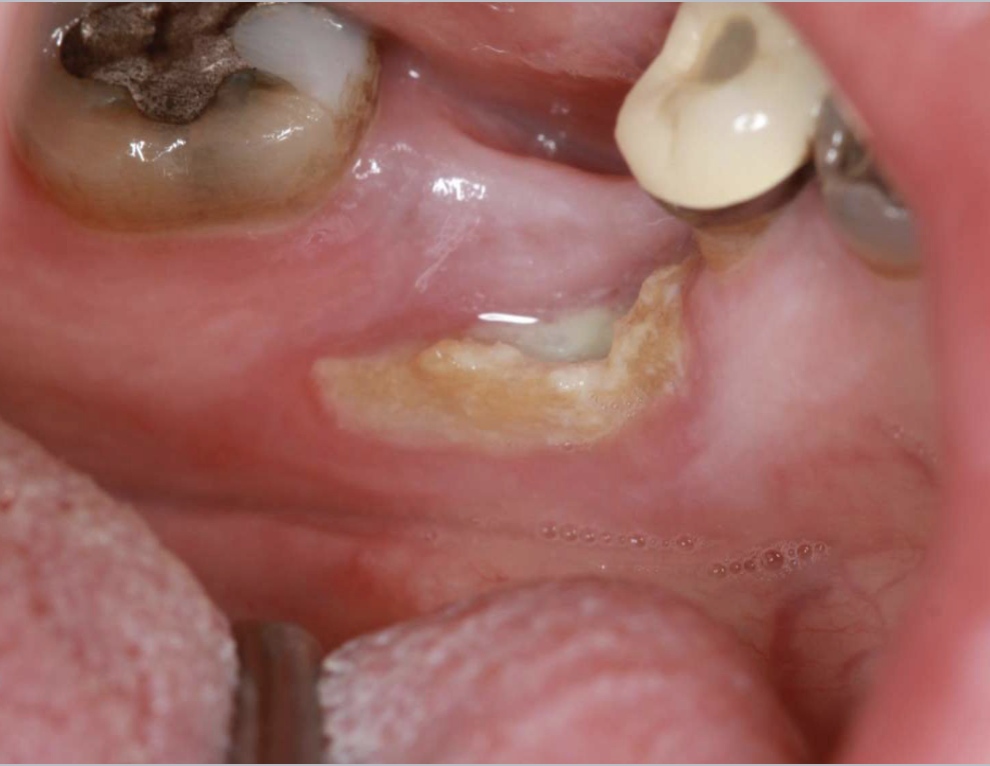

what is this

medication-related osteonecrosis of the jaws (MRONJ)